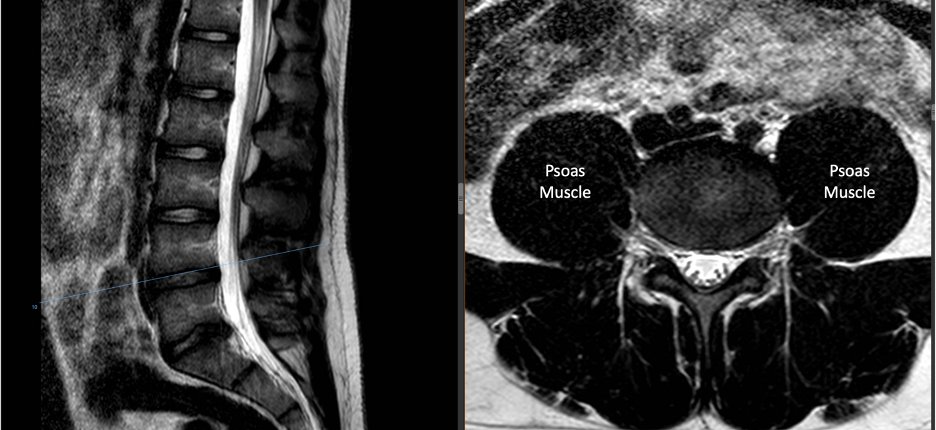

THE PSOAS INDEX, also known as the psoas muscle area or psoas muscle cross-sectional area, is a measurement used to assess muscle mass and function, particularly in the context of sarcopenia and frailty. It specifically focuses on the psoas muscle, which is a major muscle located